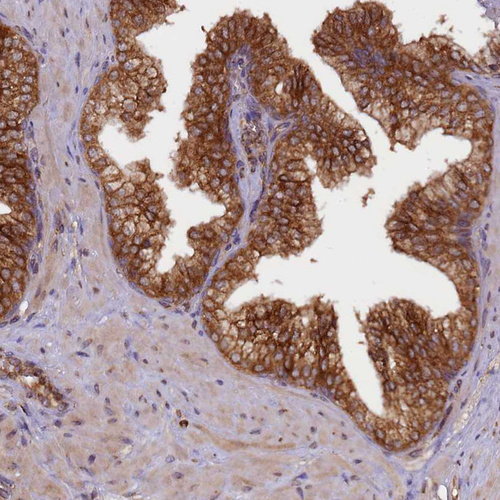

Immunohistochemical staining of human endometrium shows strong cytoplasmic positivity in glandular cells.